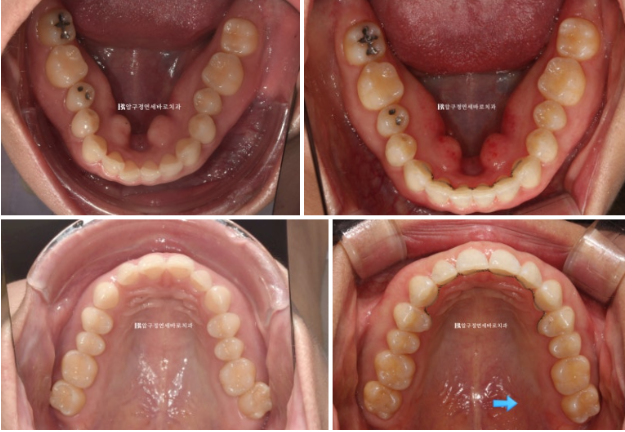

23.07

중심선 불일치 그리고 오른쪽의 맨 뒤 큰 어금니가 바깥으로 나가 있는 가위교합이 정면에서도 잘 보입니다.

오른쪽 맨 뒤 큰 어금니의 가위교합이 보이고 왼쪽은 송곳니와 앞니 사이 벌어진 공간이 보입니다.

23년 7월부터 23년 12월까지 약 5개월에 걸쳐서 1차 세트 장치 14개를 다 착용한 후 모습입니다.

23.12

가위교합과 벌어졌던 공간은 이미 해결이 되었습니다.

중심선도 잘 맞습니다.

23.07~24.05

가위교합이었던 우측 상악 제 2대구치 교합도 잘 유지가 되고 있습니다.

악궁 모양과 배열이 잘 잡혔고 재제작때 미니스크류 뺀 자리는 잘 아물어서 흔적이 없습니다.